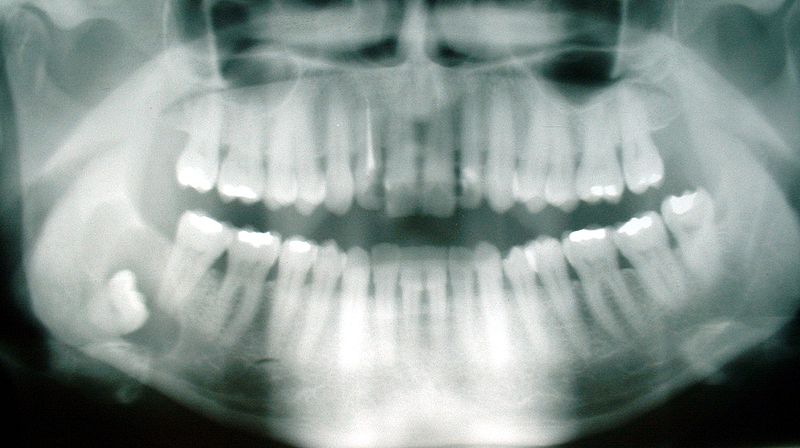

그러나 발치가 아무리 단순하게 보일지라도 치과 추출 전에 나머지 해부학적 상태의 위치를 방사선 사진으로 확인해 보는 것이 좋습니다.